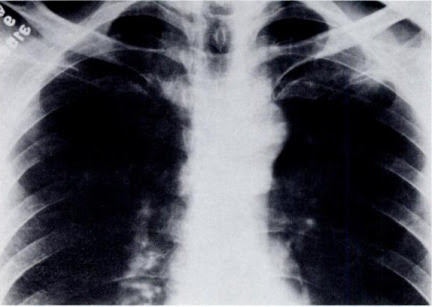

thickening pleural bmj bilateral pleura investigating calcified e8376

Investigating Pleural Thickening | The BMJ

Investigating pleural thickening | The BMJ www.bmj.com